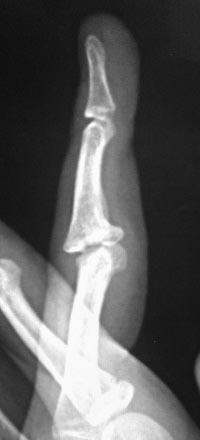

Неправильно сросшийся эпифизиолиз средней фаланги пальца кисти.

Разгибательная

контрактура

Приветствую, коллеги! Девочка 14 лет. В июле 2016 года ударила палец о

мяч. Лечились гипсовой иммобилизацией 4 недели и всё. Обратились через 5

месяцев, с жалобами на сохранившееся ограничение сгибания.

При осмотре: сгибание в проксимальном межфаланговом суставе 3

пальца кисти на 90 градусов. На рентгенограммах: фрагментарный перелом

волярой части эпифиза со смещением на первичных снимках, сохранившееся

(усилившееся) через 5 месяцев. Состояние подвывиха.